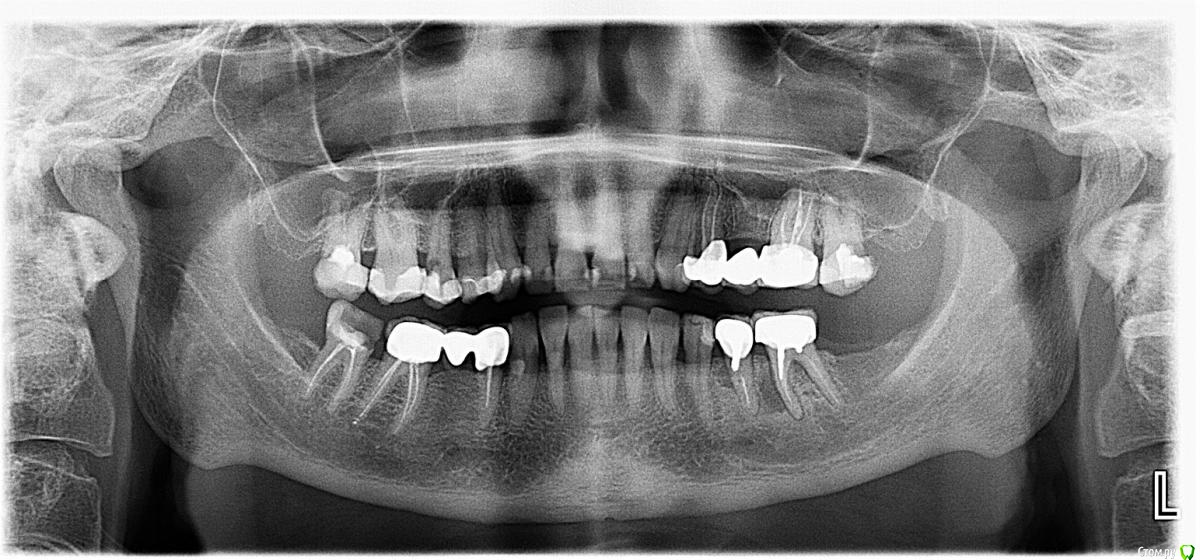

Silver80 Опубликовано 9 марта, 2018 Поделиться Опубликовано 9 марта, 2018 Добрый день, уважаемые стоматологи! помогите пожалуйста разработать грамотный план протезирования для мамы. интересует какие зубы нужно пролечить, какие под коронки, какие удалить и в последующем имплантировать. жалобы: интересуют больше всех- 27 зуб(можно ли под коронку)- один ортопед сказал, что на снимке ОПТГ видит кариес который пошел на корень и его надо удалять-17 зуб(можно ли под коронку) - откололся до десны, тоже сказали удалять. тк увидели воспаление на корне большое на ОПТГ????-все остальные зубы верхней челюсти-есть ли под пломбами скрытые кариозные процессы, которые надо пролечить? мб какие-то зубы пора накрыть коронками?НИЗ:- в каком состоянии 44 зуб?- можно ли вкладку и коронку на 47 зуб?- между 35 и 36 периодически надувается гнойная шишечка, потом проходит. не шатаются, не болят. там есть какие-то проблемы? возможно ли их сохранить. спасибо большое всем ответившим http://my-files.ru/0dwj9d Ссылка на комментарий

Silver80 Опубликовано 10 марта, 2018 Автор Поделиться Опубликовано 10 марта, 2018 снимок ОПТГ Ссылка на комментарий

DmitrySH Опубликовано 10 марта, 2018 Поделиться Опубликовано 10 марта, 2018 27 зуб(можно ли под коронку)- один ортопед сказал, что на снимке ОПТГ видит кариес который пошел на корень и его надо удалять Скорее всего так оно и есть -17 зуб(можно ли под коронку) - откололся до десны, тоже сказали удалять. тк увидели воспаление на корне большое на ОПТГ???? Воспаление можно вылечить. Но прогноз недолговременный из-за дефицита тканей. в каком состоянии 44 зуб? в сомнительном - можно ли вкладку и коронку на 47 зуб? можно, но сперва ревизию каналов сделать. - между 35 и 36 периодически надувается гнойная шишечка, потом проходит. не шатаются, не болят. там есть какие-то проблемы? возможно ли их сохранить. Проблема и с тем и с другим. Пора удалять. есть ли под пломбами скрытые кариозные процессы, которые надо пролечить? 15, сильно разрушен. сохранение под большим вопросом Ссылка на комментарий

Silver80 Опубликовано 11 марта, 2018 Автор Поделиться Опубликовано 11 марта, 2018 DmitrySH, большое спасибо за комментарии. скажите пожалуйста, а с 14 зубом все нормально? там нет такого же процесса как и в 15? просто про 15 зуб-вообще в шоке. ничего не болит. не под коронкой. как он так незаметно разрушился. а с верхними центральными все нормально? Ссылка на комментарий

DmitrySH Опубликовано 11 марта, 2018 Поделиться Опубликовано 11 марта, 2018 с 14 зубом все нормально на снимке не видно а с верхними центральными все нормально Ничего особенного, по снимку небольшие дефекты пломб, лучше очно смотреть. Ссылка на комментарий